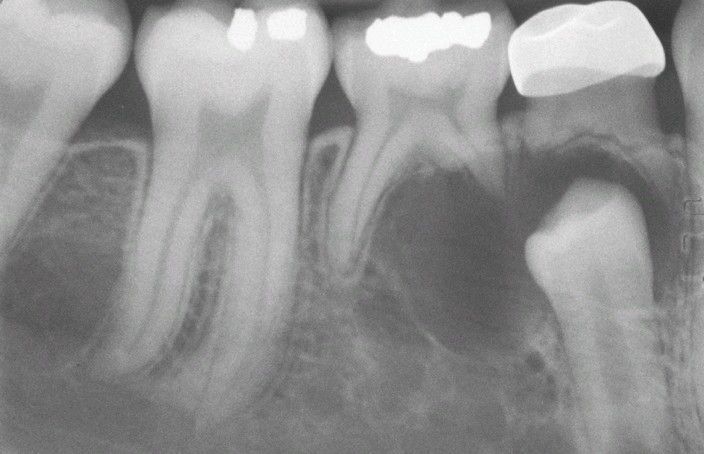

Odontogenic Keratocyst (OKC).

This cyst involves the crown of an unerupted premolar. Radiographically, this lesion cannot be differentiated from a dentigerous cyst.